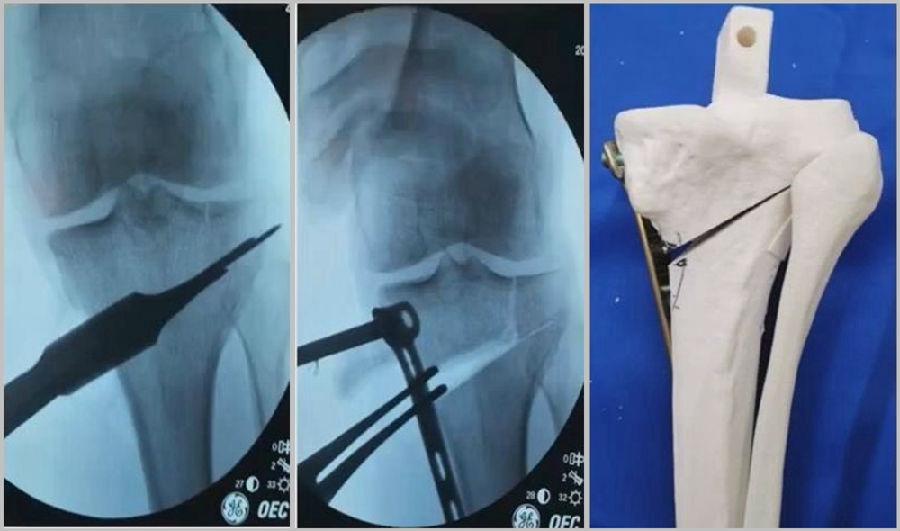

(3)Ⅲ型骨折

首先要把截骨撑开钳拿下来,此时骨折端会自动复位,然后再由外向内侧打入一颗拉力螺钉,将胫骨平台做临时固定,然后再进一步的用摆锯锯或是用骨刀打,保留1cm的合页,最后再进行撑开,做内固定。同样要求患者做结构植骨加延迟负重。

截骨偏前,截骨线过短;Ⅲ型骨折;保留1cm合页

结构植骨,外侧拉力钉固定